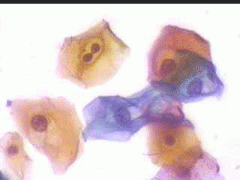

6.9.2002 Μετά από πάροδο διετίας επανέρχεται για προληπτικό έλεγχο.. Στο ιστορικό μικρο-υποτροπές κολπίτιδας, που ξεπερνούσε παροδικά με 3ήμερη χρήση Daktarin vag. supp. Το κολποσκοπικο εύρημα ήταν φυσιολογικό, ωστόσο το κυτταρολογικό επίχρισμα εμφάνιζε την τυπική πολυμορφία ερπητικών αλλοιώσεων.

4.8.2005 σε 2-3 οπτικά πεδία κυτταρολογικές ατυπίες που συνηγορούν για ερπητικές αλλοιώσεις ..

Στις 27.4.2010 εκ νέου σποραδική διακριτική κοιλοκυτταρική ατυπία και χαρακτηριστικές ατυπίες πυρηνων, που συνηγορούν, σε συνάρτηση με το ιστορικό, για ερπητικές αλλοιώσεις.